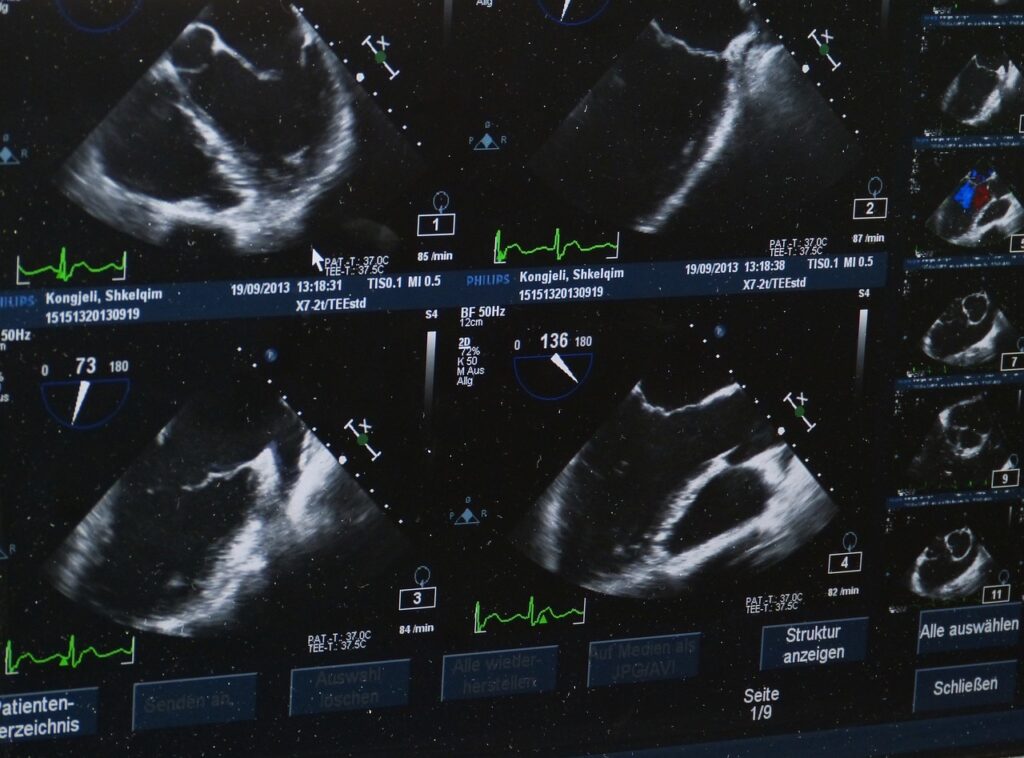

Si vous lui avez annoncé qu’il allait “voir le bébé”, il sera généralement très déçu par les images de l’échographie. Ces dernières sont bien souvent incompréhensibles pour lui. D’ailleurs, il est fort probable que vous ne reconnaissiez pas grand-chose non plus, mis à part le fameux cliché du bébé “de profil” ! Votre tout-petit pourra alors se trouver perturbé quand il réalisera que vous regardez attentivement un écran sur lequel il ne verra rien qui ressemble à sa conception d’un bébé. Fort déçu, il risquera de se montrer désagréable et de tenter d’attirer l’attention à lui, ce qui est tout à fait normal mais dès lors, vous serez condamnés à tenter de captiver son attention en lui parlant ou en commentant les images.